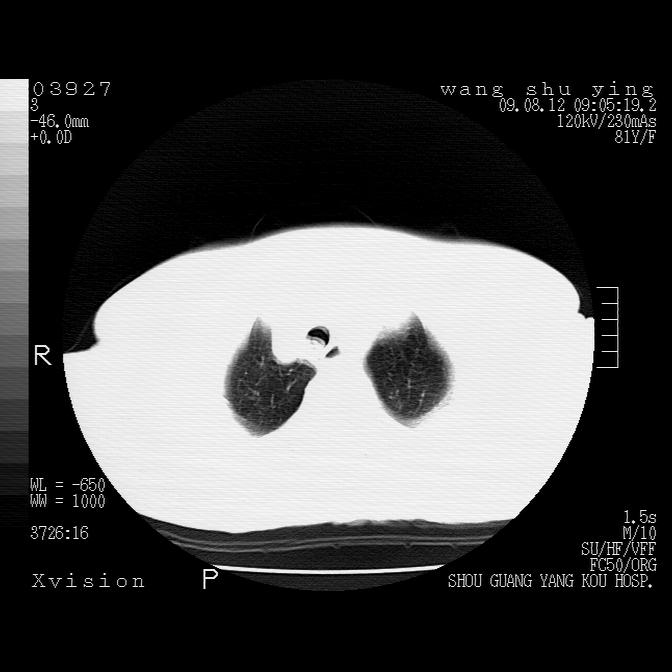

以下是引用帅河马在2009-8-12 12:59:00的发言:[br]两肺感染性病变伴双侧胸膜肥厚。[br]左侧甲状腺腺瘤不除外。[br]腹水+心包积液。[br][br][本贴已被 帅河马 于 2009-8-12 13:14:32 修改过]

以下是引用sdzyy在2009-8-12 18:17:00的发言:[br]两肺感染性病变伴双侧胸膜肥厚。[br]左侧甲状腺腺瘤不除外。[br]腹水+心包积液。[br]支持

以下是引用随光逐影在2009-8-12 19:42:00的发言:[br]1)两肺感染性病变伴双侧胸膜肥厚。2)不排除左侧甲状腺腺瘤。3)肝脏占位性病变;建议行进一步检查。